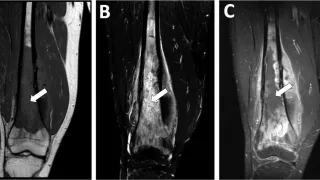

手術日+658日目 2025/12/17(水)(骨肉腫のMRI)

午前の病院での仕事昨晩は小雨でしたが, 今朝は一転して青空.雲の切れ間から陽射しが差し込み, 少し気分が軽くなる朝でした.8時前に病棟に上がり, 昨日後輩医師の執刀で手術が行われた患者さん2人(変形性膝関節症に対する単顆型人工膝関節部分置換...